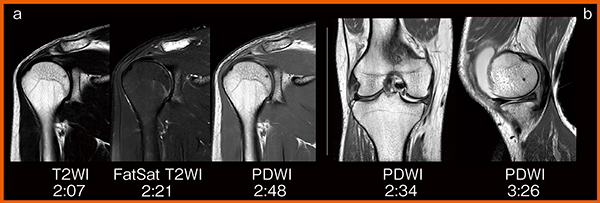

ECHELON Smart Plusでは高速撮像技術IP-RAPIDにより,高画質を維持しつつ撮像時間を短縮できるようになった。頭部ルーチン撮像では,各シーケンスを1〜2分程度で撮像でき,ポジショニングも含めて約15分で検査を終了できる。また,脊椎検査ではT2強調画像と脂肪抑制画像を同時に取得できる“FatSep”併用により,約13分で一通りの画像を得ることができる。関節領域においても短時間で明瞭な画像を得られている(図1)。

図1 関節へのIP-RAPIDの適用

短時間撮像でも,FatSatによる脂肪抑制(a)やプロトン密度強調画像(b)で

信号変化を明瞭にとらえている。